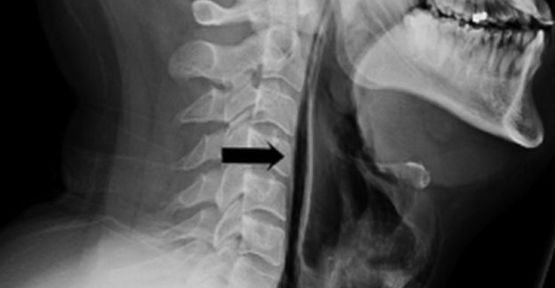

Çekilen röntgen sonucu, nefes borusundan kaçan havanın boğazındaki yumuşak doku ve boyuna gittiği anlaşıldı. Hasta, dokular iyileşene dek yedi gün boyunca bir tüple beslenmek zorunda kaldı ve daha sonra taburcu edildi. Hastanın tedavi edildiği Leiceste’daki hastanenin Kulak Burun Boğaz bölümündeki doktorlar ise, “Burun ve ağzı kapatarak hapşırığı durdurmak tehlikeli bir şey ve kesinlikle yapılmamalı” diyor. (BBC Türkçe)